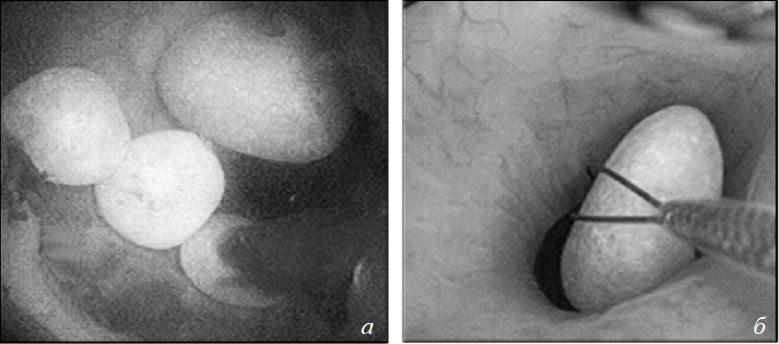

Образование конкрементов в свободном растворе

В хирургической практике довольно часто обнаруживаются свободно лежащие в полостной системе почки камни, даже без намека на их открепление от сосочка. Имеются в виду камни CaOx при ПГ 1-го типа после шунтирующих операций по поводу ожирения, большинство БР- и ГА-камней и все цистиновые камни (рис. 9). В случае с микролитами в ВМСК при цистинурии застой мочи действует как питательная среда для камнеобразования. Также возможен рост камня после нуклеации при условии нарушения оттока мочи. Эти мысли если не полностью, то частично подтверждают гипотезу заглушек, согласно которой эти микрочастицы задерживаются в дистальных отделах канальцев и увеличиваются в размерах. Несомненно, множество различных кристаллов образуются в моче, подтверждение чему мы находим в многочисленных анализах мочи. Но проблема в том, что никто из нас никогда не наблюдал превращения этих кристаллов в конкременты, хотя эта идея давно уже витает в воздухе. У нас попросту не хватает весомых экспериментальных подтверждений либо опровержений этой гипотезы, без чего она остается всего лишь теорией.

Рис. 9. Цистиновые конкременты: а) свободно лежащие конкременты — эндоскопический вид; б) цистиновые камни, абсолютно гладкие, овальной формы, имеют гомогенную желтую окраску